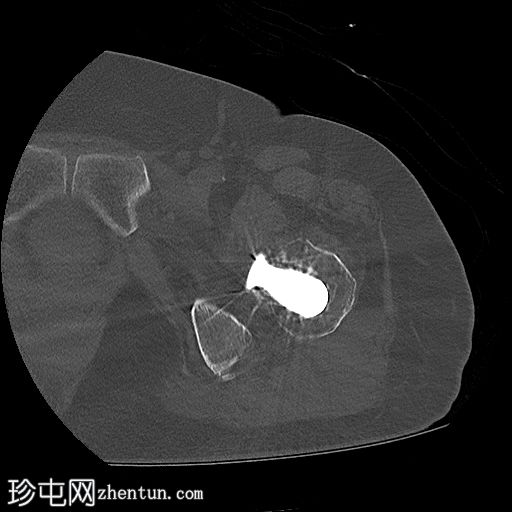

CT

轴位骨窗

左侧全髋关节置换术。大转子基底部可见轻微移位的假体周围骨折。

大转子滑囊积液,可见脂肪-液体平面。